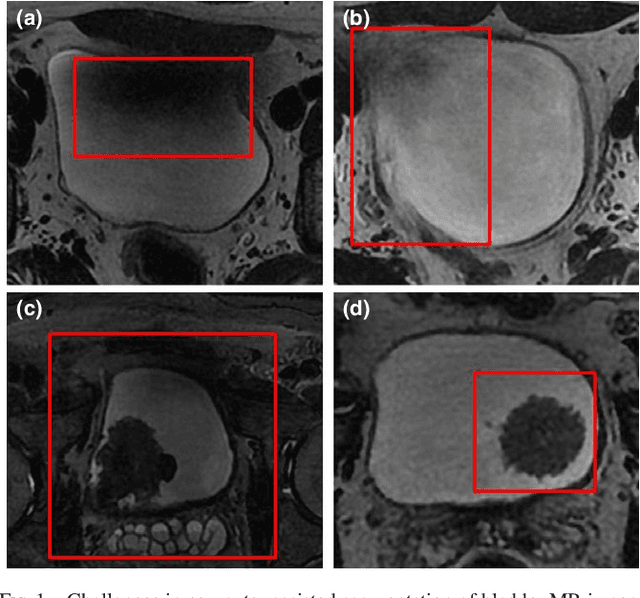

Abstract:Precise segmentation of bladder walls and tumor regions is an essential step towards non-invasive identification of tumor stage and grade, which is critical for treatment decision and prognosis of patients with bladder cancer (BC). However, the automatic delineation of bladder walls and tumor in magnetic resonance images (MRI) is a challenging task, due to important bladder shape variations, strong intensity inhomogeneity in urine and very high variability across population, particularly on tumors appearance. To tackle these issues, we propose to use a deep fully convolutional neural network. The proposed network includes dilated convolutions to increase the receptive field without incurring extra cost nor degrading its performance. Furthermore, we introduce progressive dilations in each convolutional block, thereby enabling extensive receptive fields without the need for large dilation rates. The proposed network is evaluated on 3.0T T2-weighted MRI scans from 60 pathologically confirmed patients with BC. Experiments shows the proposed model to achieve high accuracy, with a mean Dice similarity coefficient of 0.98, 0.84 and 0.69 for inner wall, outer wall and tumor region, respectively. These results represent a very good agreement with reference contours and an increase in performance compared to existing methods. In addition, inference times are less than a second for a whole 3D volume, which is between 2-3 orders of magnitude faster than related state-of-the-art methods for this application. We showed that a CNN can yield precise segmentation of bladder walls and tumors in bladder cancer patients on MRI. The whole segmentation process is fully-automatic and yields results in very good agreement with the reference standard, demonstrating the viability of deep learning models for the automatic multi-region segmentation of bladder cancer MRI images.